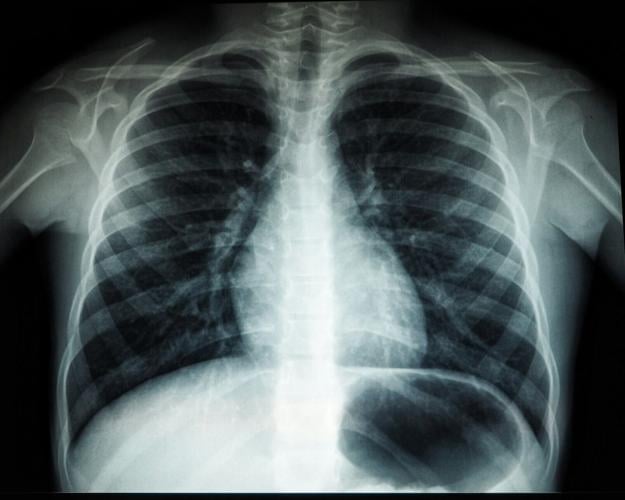

It could enable doctors to diagnose infections such as pneumonia much quicker - without the need for invasive blood tests, according to a new study.

Initial experiments demonstrated the approach in animals with pneumonia and infections in the bloodstream, muscles and bones.

Wilson said: "When mice with infections such as pneumonia and bone, muscle, or blood infections received intravenous injections of these tagged compounds, the animals’ breath quickly showed elevated levels of the labelled carbon dioxide."